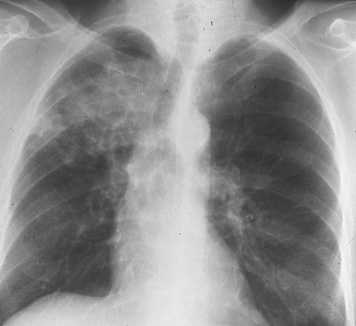

Fig. 44a: Posterior-anterior chest radiograph shows a mass in the right upper lobe and a mass in the right hilum. Mediastinal involvement cannot be excluded. Questionable T2 N2 M0 disease.